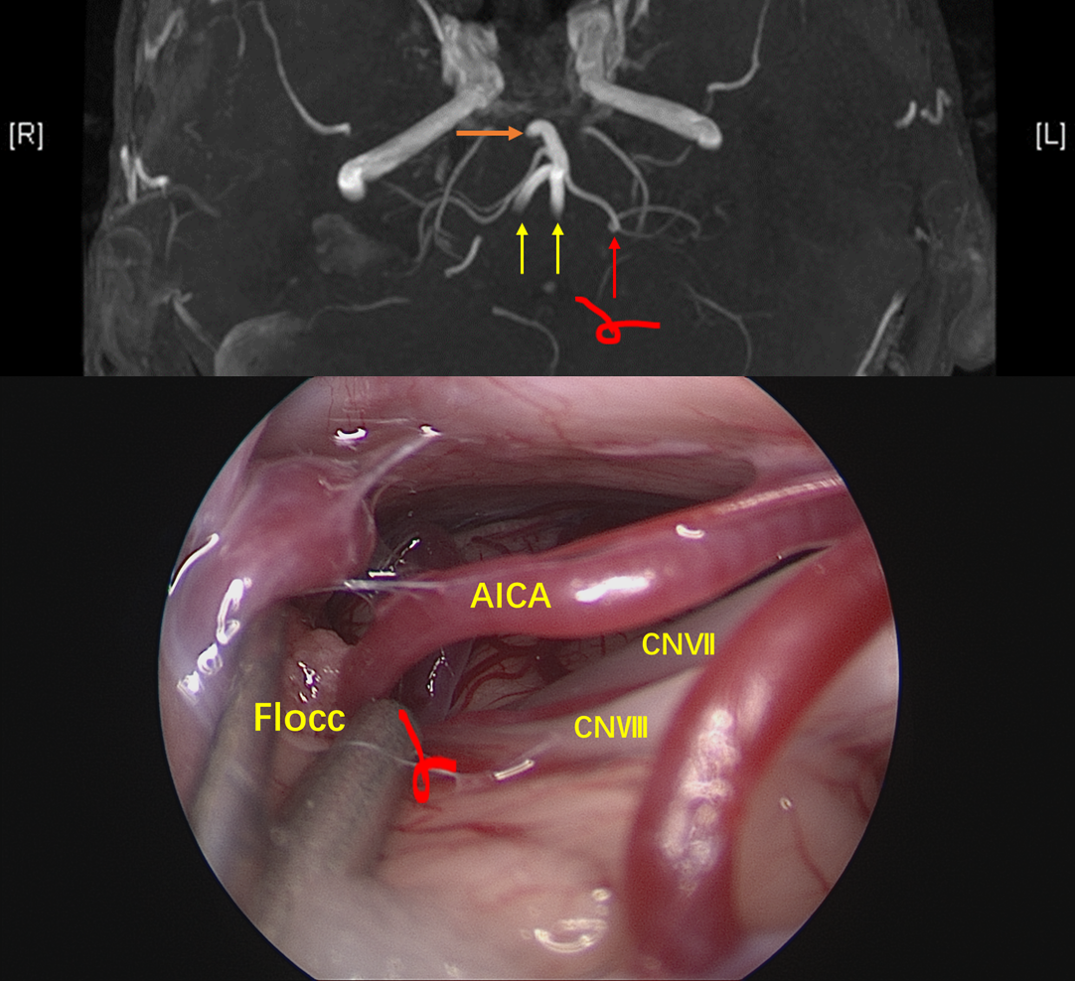

神经内镜经绒球下入路到桥小脑角区,可见AICA弯曲成袢压迫面神经出脑干处,与影像学所见一致。

松解周围蛛网膜,抬起AICA可见面神经上有明显压痕。

神经内镜抵近观察,与术前影像一致,PICA从VA发出后于下方呈袢,压迫面神经出脑干处。

Tefflon垫绵充分减压。再次观察,PICA如我们所见,迂曲呈“S”型,再于后组颅神经后方(手术视角)绕回,与小脑后下动脉走行特点相吻合。